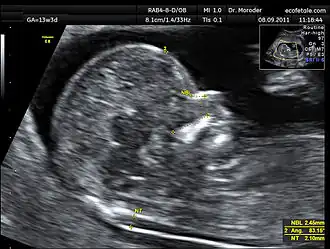

Procedure

Nuchal scan (NT procedure) is performed between 11 and 14 weeks of gestation, because the accuracy is best in this period. The scan is obtained with the fetus in sagittal section and a neutral position of the fetal head (neither hyperflexed nor extended, either of which can influence the nuchal translucency thickness). The fetal image is enlarged to fill 75% of the screen, and the maximum thickness is measured, from leading edge to leading edge. It is important to distinguish the nuchal lucency from the underlying amniotic membrane.[9]

Normal thickness depends on the crown-rump length (CRL) of the fetus. Among those fetuses whose nuchal translucency exceeds the normal values, there is a relatively high risk of significant abnormality.

How to define a normal or abnormal nuchal translucency measurement can be difficult. The use of a single millimeter cutoff (such as 2.5 or 3.0 mm) is inappropriate because nuchal translucency measurements normally increases with gestational age (by approximately 15% to 20% per gestational week from 10 to 13 weeks).[10] At 12 weeks of gestational age, an "average" nuchal thickness of 2.18mm has been observed; however, up to 13% of chromosomally normal fetuses present with a nuchal translucency of greater than 2.5mm. Thus for even greater accuracy of predicting risks, the outcome of the nuchal scan may be combined with the results of simultaneous maternal blood tests. In pregnancies affected by Down syndrome there is a tendency for the levels of human chorionic gonadotropin (hCG) to be increased and pregnancy-associated plasma protein A (PAPP-A) to be decreased.